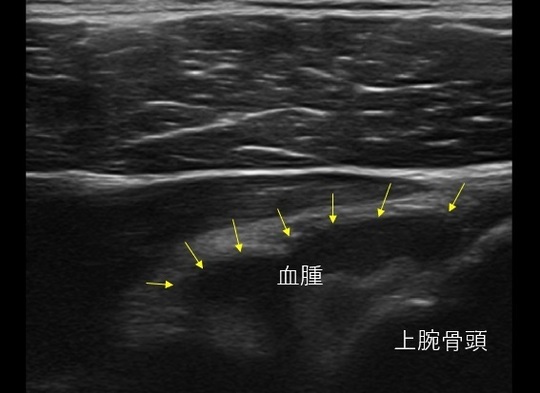

肩後方のエコー画像。後方の血腫を認める。

外旋位固定では肩関節前方の肩甲下筋によって関節内の血腫が後方に押し込まれることで、損傷している関節唇が関節窩に密着をすることにより治癒を目指します。